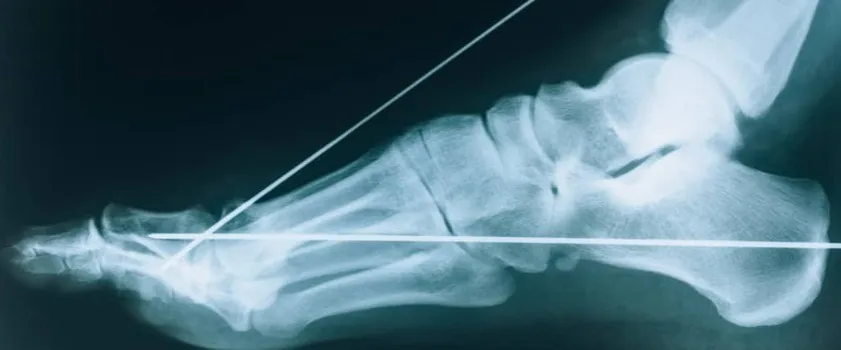

Jeśli ból jest tak silny, że całkowicie uniemożliwia postawienie stopy na ziemi, a obrzęk jest bardzo duży i szybko narasta, zawsze należy podejrzewać złamanie. W takiej sytuacji lekarz niemal zawsze zleci badanie RTG. To kluczowe, aby wykluczyć uszkodzenie kości, ponieważ postępowanie w przypadku złamania jest zupełnie inne niż przy skręceniu. Nie można ryzykować błędnej diagnozy, która mogłaby prowadzić do poważnych komplikacji.

RTG czy USG? Jakie badania pomagają ocenić skalę uszkodzeń?

W celu wykluczenia złamania kości, lekarz często zleca badanie RTG (rentgen). Jest to podstawowe badanie, które pozwala mi ocenić stan struktur kostnych. Jeśli jednak podejrzewam poważniejsze uszkodzenie więzadeł, torebki stawowej lub innych tkanek miękkich, standardem staje się badanie USG (ultrasonografia). USG pozwala mi precyzyjnie ocenić ciągłość więzadeł, obecność płynu w stawie czy uszkodzenia chrząstki, co jest niezwykle ważne dla postawienia pełnej diagnozy i zaplanowania skutecznej rehabilitacji.